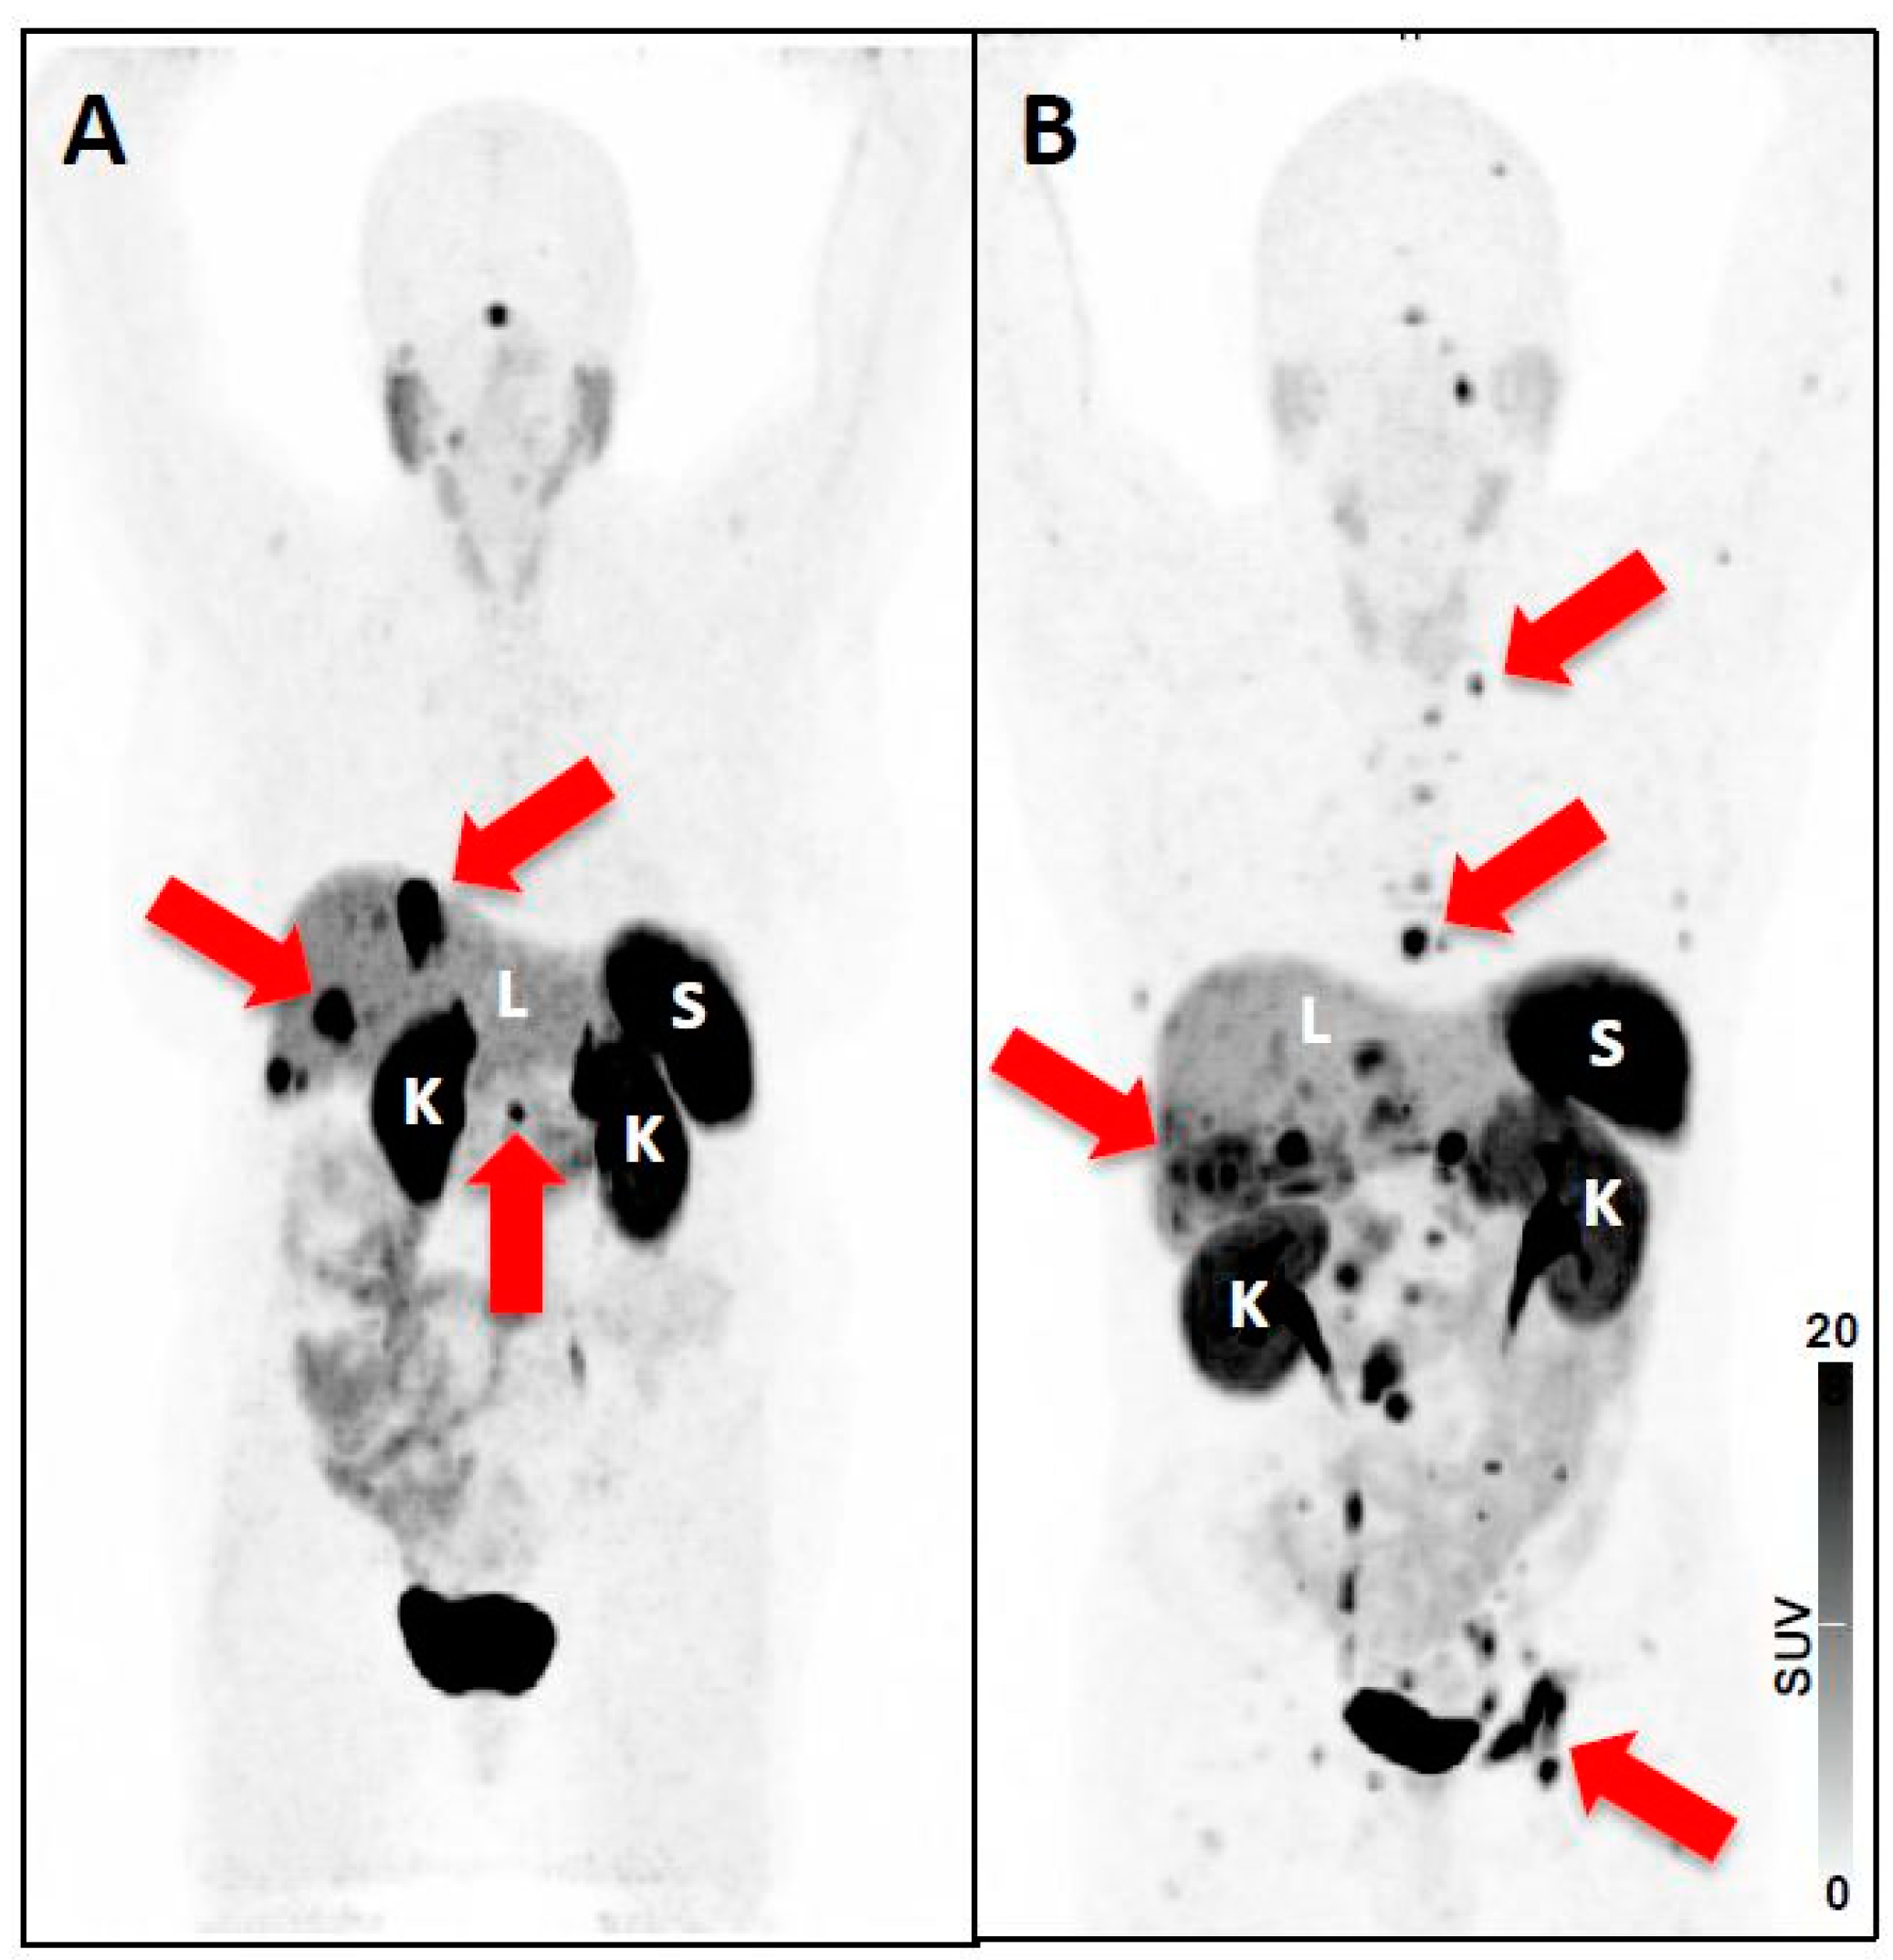

- Beauregard, J.M.; Hofman, M.S.; Kong, G.; Hicks, R.J. The tumour sink effect on the biodistribution of 68Ga-DOTA-octreotate: Implications for peptide receptor radionuclide therapy. Eur. J. Nucl. Med. Mol. Imaging 2012, 39, 50–56. [Google Scholar] [CrossRef] [PubMed]

- Werner, R.A.; Hanscheid, H.; Leal, J.P.; Javadi, M.S.; Higuchi, T.; Lodge, M.A.; Buck, A.K.; Pomper, M.G.; Lapa, C.; Rowe, S.P. Impact of tumor burden on quantitative [(68)Ga] DOTATOC biodistribution. Mol. Imaging Biol. 2018. [Google Scholar] [CrossRef]